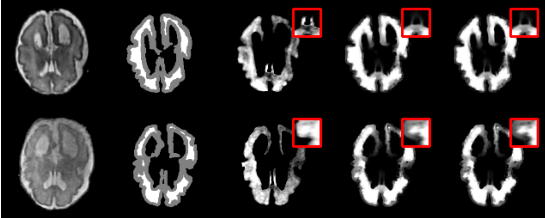

强先验方法:目前主流的深度学习方法通常需要大量的像素级标注数据(强先验),但这在医学影像领域获取成本高昂且困难。 弱先验方法:利用如三分图这样的弱先验信息进行抠图,标注成本低,这些方法包括: l 基于传播的方法:依赖于平滑性假设,即像素在特定区域变化平滑。如果自然图像中存在违反该假设的情况(如纹理复杂),预测精度会受限。 l 基于采样的方法:依赖于从未知像素的周边选取像素对子集。如果子集中的像素对与最优解差异较大,抠图精度会迅速下降。 l 优化类方法:将医学图像抠图问题建模为像素对选择问题,从整个像素对集合中选择像素对。进化算法因其强大的全局优化能力被用于求解像素对选择问题,能够更广泛地搜索解空间,而不局限于局部区域或特定的初始采样质量。然而,像素对选择问题的决策空间规模随着未知像素数量的增加呈指数级增长,增加了进化算法陷入局部最优的风险,降低了进化算法的求解效率。 2. 方法概述 针对上述挑战,智能算法研究中心与南方医科大学附属南方医院庄宝雄教授团队合作提出了一种用于求解医学图像抠图问题的微搜索进化优化框架[1][2]。 微搜索假设被广泛应用于众多优化问题的求解中,如滤波器自动调参问题[11],双层车辆路径规划问题[10],约束优化问题[9]等。实验结果验证了微搜索假设能够帮助算法大幅度提升算法求解问题的效率。在微搜索假设中,对于任意一种算法,决策空间(决策集)中存在一个规模远小于决策空间(决策集)的子空间(子集),该子空间(子集)由算法的可行解组成,且包含了优化问题的最优解。该子空间(子集)被称为有效决策子空间(子集)。 研究团队观察到,在医学图像抠图问题中,相似的子问题(即相似的未知像素)其目标空间也具有高度的相似性(图 1),目标函数在梯度方向和数值分布上都高度一致。这意味着进化算法在优化相似子问题时,同一个解所在的局部区域为进化算法提供的启发式信息是子问题无关的。

图 1 相似子问题的目标空间等高线对比